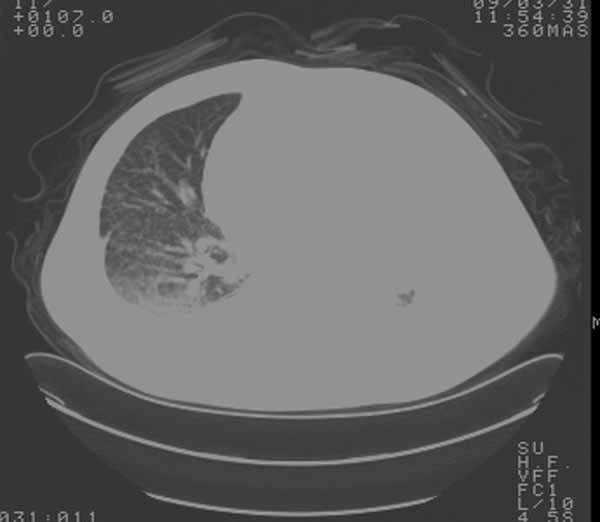

以下是引用余辉在2009-3-31 18:43:00的发言:[br]肺水肿,双侧心腔积液,心包积液,心影增大,疑似心衰

以下是引用wangyong1977在2009-3-31 20:46:00的发言:[br]肺水肿,双侧胸腔积液,心包积液,心影增大,疑似心衰 [br]

以下是引用宇宙ct在2009-3-31 18:57:00的发言:[br]肺水肿,双侧心腔积液,心包积液,心影增大,疑似心衰 [br] [br]